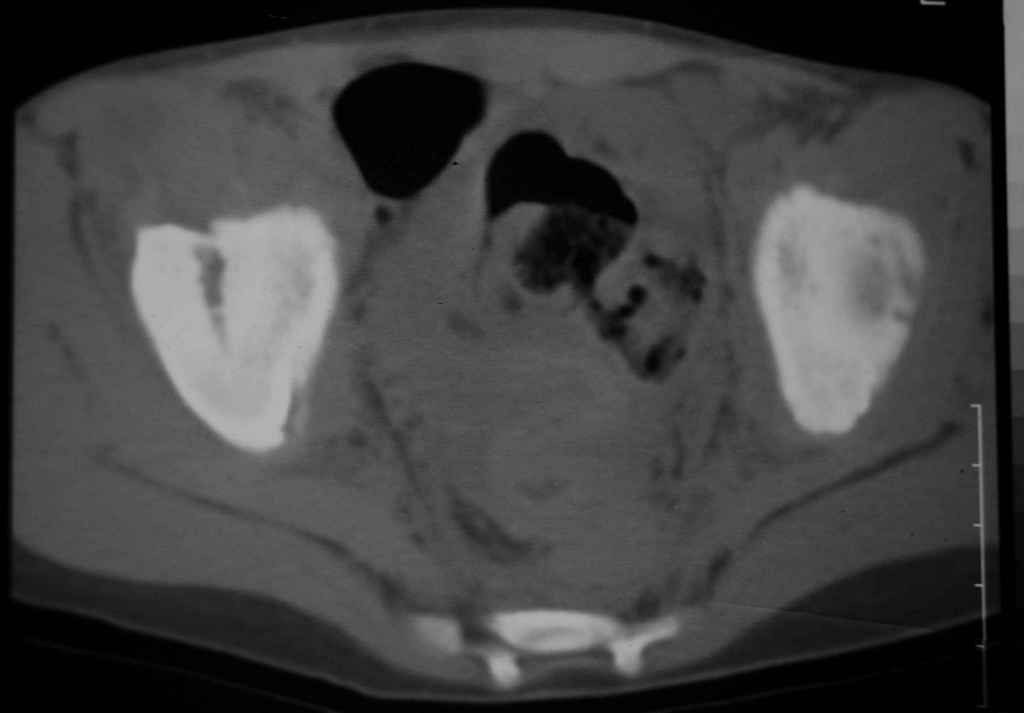

Перелом вертлужной впадины

Уважаемые коллеги, помогите определиться с тактикой лечения.Ребёнок 7 лет, травма 11.09.08, поступил с травматическим вывихом бедренной кости.

Вывих вправлен, конечность фиксирована на скелетном вытяжении. Что делать с переломом подвздошной кости? Лечить консерватино или оперировать?